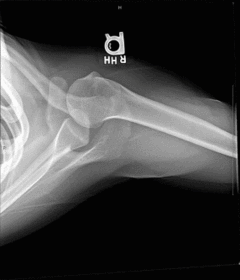

| Lateral Elbow | The elbow is elevated above the level of the shoulder radial head anterior to coronoid - should be superimposed capitulum too proximal to trochlea radial tuberosity seen - hand is pronated |

| Lateral Elbow | Elbow is depressed below the level of the shoulder radial head superimposed by coronoid capitulum too distal to medial trochlea |

| Lateral Elbow | the distal wrist is elevated hand is pronated because you can see the radial tuberosity - should not see that |

| Lateral Elbow Evaluation Criteria | ANATOMY: distal humerus, proximal forearm, entire elbow joint CRITERIA: humeral epicondyles are superimposed radial tuberosity is invisible (if visible the hand is pronated) half of the radial head superimposed by coronoid process Elbow is flexed 90 degrees to see/not see fad pads 3 concentric arcs visible POSITIONING: CR perpendicular @ lateral epicondyle |